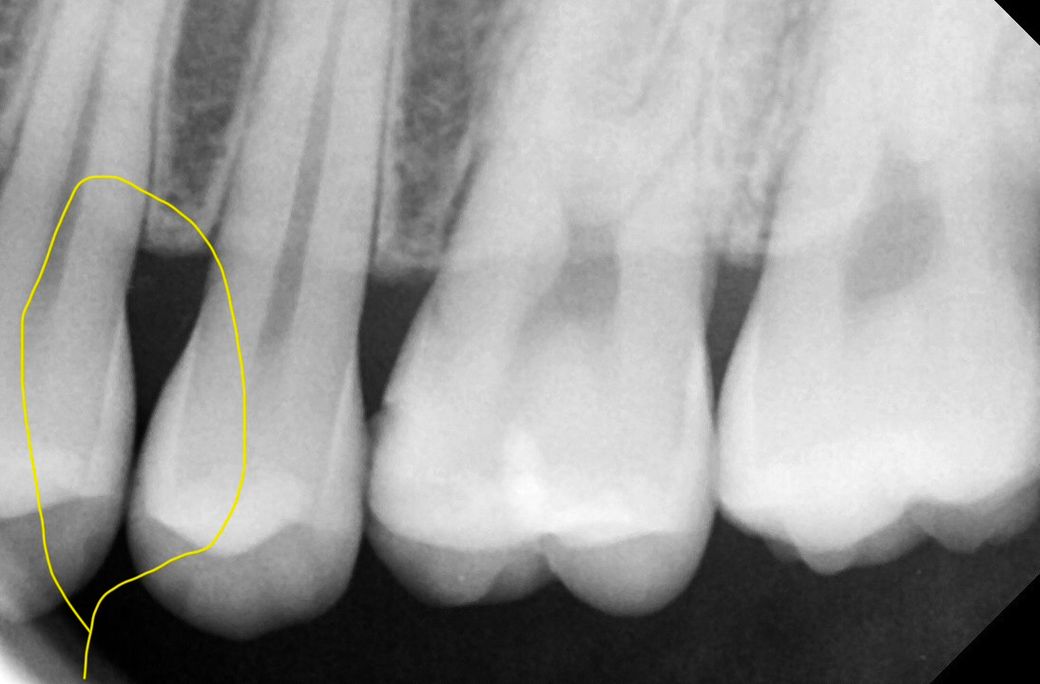

인접면 충치 봐주세요 임상 치근단 교익 있어요

치과 4군데를 돌아 치근단을 찍어보고

인접면 충치를 잘 잡는다는 교익 촬영까지 했습니다

• 1번 째 사진

교익방사선 촬영을 통해서 해당 부위의 미세한 충치가 있기는 합니다. 하지만 이 부위를 치료하기 위해서는 더 큰 치질을 손상시켜야 하므로 치간칫솔이나 치실을 사용하면서 해당 부분을 관찰하는 것이 좋을 수 있습니다. 지금의 충치 정도로는 큰 불편감이 나타날 가능성은 적습니다. 아마 심리적인 요인일 가능성이 커 보입니다.

1. 사진 좌우 반전되거나 수정한게 아니라면 임상사진은 15,14번이고, 방사선 사진은 24,25 입니다

2. 14,15는 명백히 충치 있어보입니다